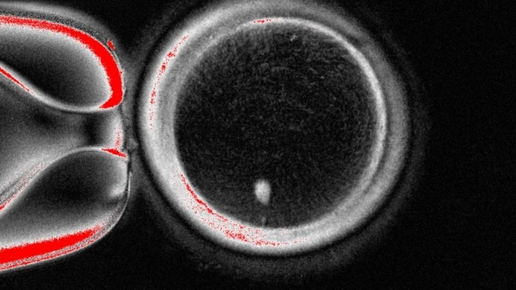

Американским и корейским ученым удалось получить человеческие яйцеклетки с гаплоидным набором хромосом путем переноса ядра соматической клетки кожи в донорскую яйцеклетку без ядра и манипуляций с делением получившейся клетки. Оплодотворение таких яйцеклеток сперматозоидами приводило к образованию эмбрионов, развитие которых прервали на стадии бластоцисты. Результаты проведенного исследования опубликованы в журнале Nature Communications. Искусственное получение половых клеток (гамет) из соматических...